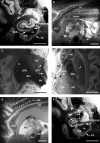

Ex vivo magnetic resonance imaging yields high resolution images that reveal detailed cerebral anatomy and explicit cytoarchitecture in the cerebral cortex, subcortical structures, and white matter in the human brain. Our data illustrate neuroanatomical correlates of limbic circuitry with high resolution images at high field. In this report, we have studied ex vivo medial temporal lobe samples in high resolution structural MRI and high resolution diffusion MRI. Structural and diffusion MRIs were registered to each other and to histological sections stained for myelin for validation of the perforant pathway. We demonstrate probability maps and fiber tracking from diffusion tensor data that allows the direct visualization of the perforant pathway. Although it is not possible to validate the DTI data with invasive measures, results described here provide an additional line of evidence of the perforant pathway trajectory in the human brain and that the perforant pathway may cross the hippocampal sulcus.